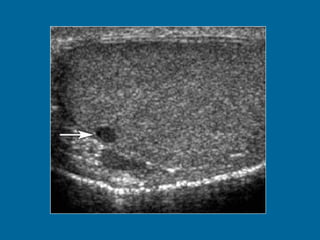

Transverse US image of the left testis shows multiple hypoechoic lesions.

Transverse US imageof the left testis shows multiple hypoechoic lesions.